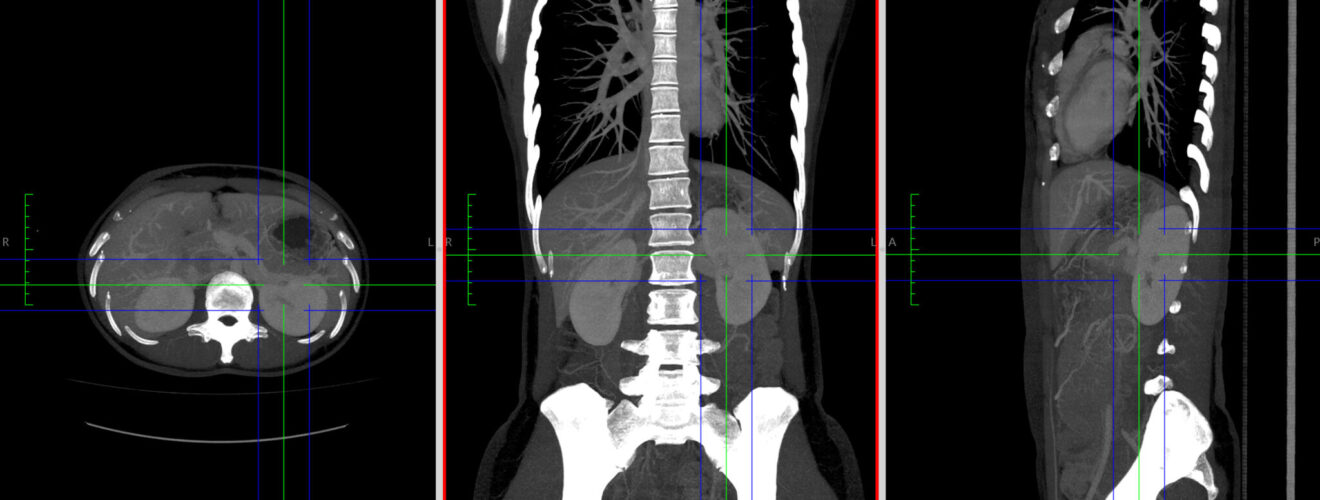

1. 解剖前に得られていたCT所見について、1つを選んで記入。2のCT画像についての説明もここに記す。どこのどの向きのスライスか、画像に追加した矢印などが何を指しているかなどを説明する。

2. 1で述べたポイントのわかるCT画像をアップロード。着目するポイントを矢印などで明示する。DICOM画像からJPEG、PNGなどの画像ファイルに書き出すこと。複数の画像を組み合わせる場合には、あらかじめ1つの画像にまとめること。10MBまで。できればファイル名を「班番号-CT」とされたい(必須ではない)